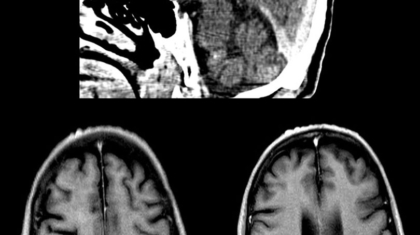

60-year-old adult, chronic smoker with history of angioplasty, presented with recent onset hemoptysis, weight loss and generalized fatigue with mild fever.